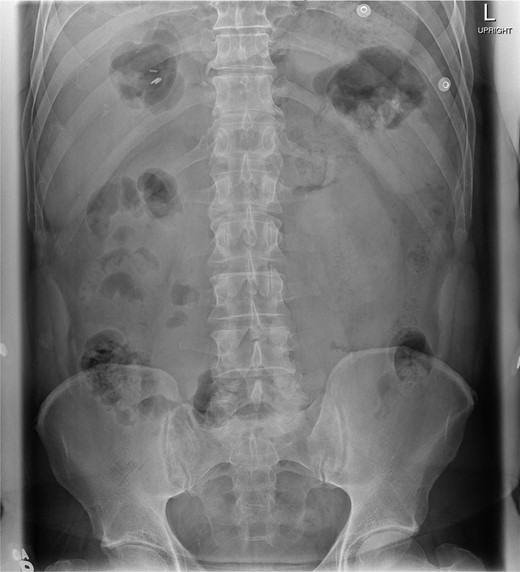

At presentation, his vitals were normal. Abdominal examination revealed an overweight gentleman with focal tenderness to the left upper quadrant. Laboratory tests revealed a WBC of 25.3 with neutrophils of 23.4. Hemoglobin, platelets, electrolytes and liver enzymes were within normal limits. Three views of the abdomen revealed no gross intra-abdominal pathology and no free air was reported on chest X-ray (Figs 1 and 2).

Chest X-ray showing left lower lobe opacity with a small volume of subdiaphragmatic free air.